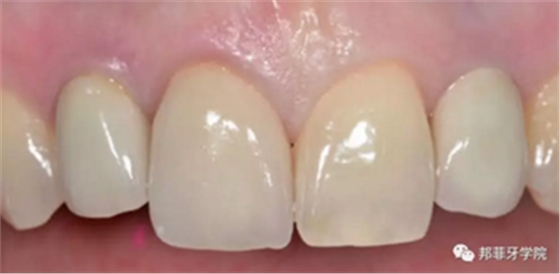

26歲女性患者,雙側上頜側切牙先天缺失,對原有修復體的“形態(tài)”、“光澤”等方面不滿意,希望重新修復(圖1&2)。12及22原為粘接橋修復,11根管治療史;拆除原修復體后余鄰牙完整,未見病理性探診深度。無系統(tǒng)疾病史?;颊咂谕递^高,告知治療流程佩戴臨時卡環(huán)義齒等(圖3)、費用、風險后表示接受治療。

圖1:治療前口內情況

6年后效果穩(wěn)定,患者滿意(圖16)。

圖 15-1:六個月后復查

圖 15-2:六個月后復查

圖 16-1: 六年后復查

圖 16-2: 六年后復查